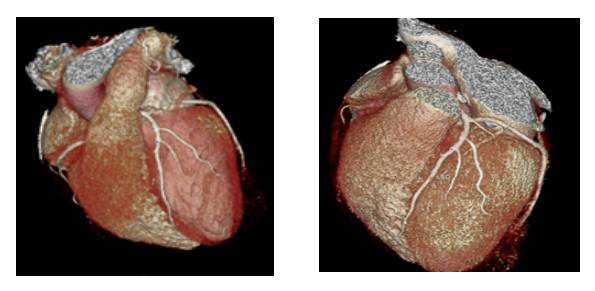

■ 表面成像(VR)

我们拿到一份冠脉CT影像首先要看VR像,从VR像我们主要是观察冠状动脉的走形、起源以及桥血管的走形。需要注意的是,VR图像不能判断冠状动脉是否狭窄,同一个人随着成像条件的变化,管腔的狭窄显示程度会发生改变。